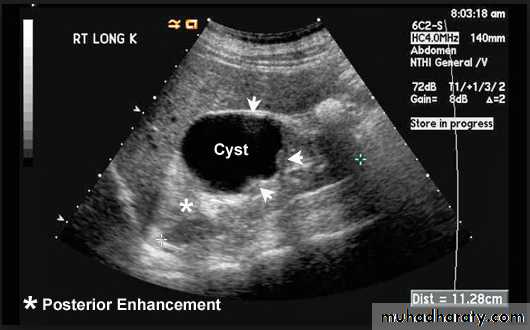

Typically, a cyst containing a clear fluid has few if any echoes (anechoic =black ) ,Tissues such as liver and spleen give a picture with rather homogeneous small echoes due to the fibrous interstitial tissue (hypo echoic , isoechoic or hyper echoic = gray scale spectrum ) ,

Renal ultrasound is a simple noninvasive examination .The kidney is bean shaped and has bright central echoes because of the fat surrounding the collecting system.

Ultrasound is typically ordered to exclude , stones , hydronephrosis or to evaluate renal size or suspected renal cysts .